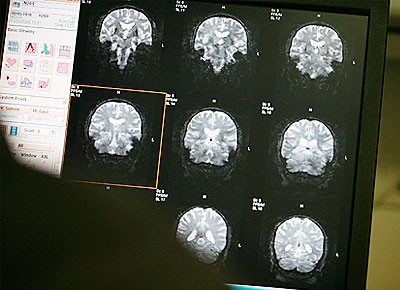

![[Img #1698]](upload/img/periodico/img_1698.jpg) En la enfermedad de Alzheimer, la proteína tóxica beta amiloide, que se acumula en el cerebro, borra recuerdos, modifica el comportamiento, y, finalmente, conduce a la muerte.

En la enfermedad de Alzheimer, la proteína tóxica beta amiloide, que se acumula en el cerebro, borra recuerdos, modifica el comportamiento, y, finalmente, conduce a la muerte.